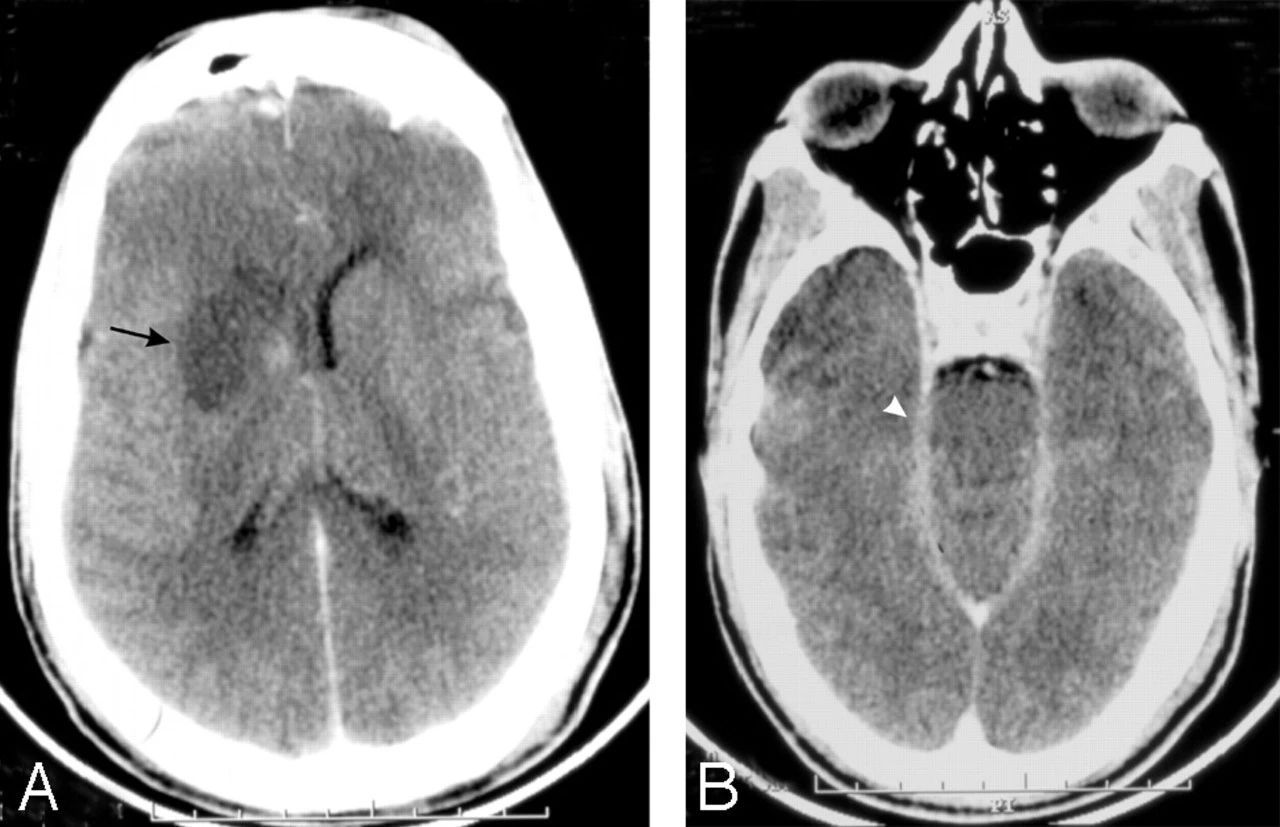

但最终导致死亡的并不是脑组织的缺失,而是身体与感染抗争所带来的发炎和肿胀,导致头骨承受着极端的压力。

巨大的压力会迫使大脑分解脑干和脊髓相连的地方,最终导致两者之间的联系被切断。大多数患者会在第二临床症状出现后因呼吸衰竭而死亡。

对比度增强的CT脑扫描显示右基底神经节梗塞(箭头,A)和增强的渗出物在脑内池(箭头,B)至于福氏耐格里阿米巴原虫为何会直接钻进大脑在科学界仍是未解之谜。